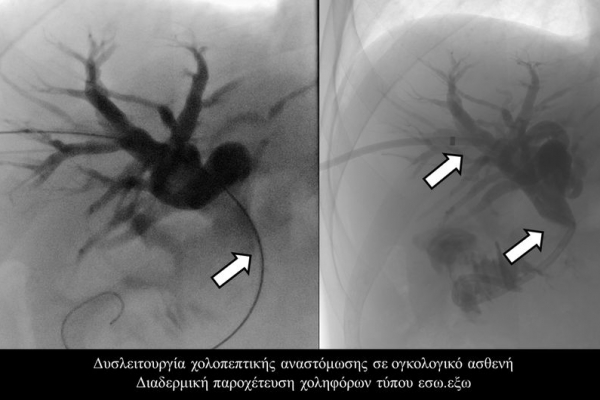

Η παροχέτευση των χοληφόρων σε αυτές τις περιπτώσεις θα πρέπει να γίνεται άμεσα, είτε ταυτόχρονα προς τα έξω και προς το 12κτυλο (έσω-έξω παροχέτευση), είτε μόνο προς τα έξω με τη βοήθεια pigtailκαθετήρα (εξωτερική παροχέτευση)

Σε περιπτώσεις όπου υπάρχει απόφραξη των χοληφόρων και ενδείκνυται η τοποθέτηση ενδοπρόθεσης (stent), τότε η βατότητα των χολαγγείων και η αντιμετώπιση του αποφρακτικού ικτέρου μπορεί να διασφαλιστεί με την τοποθέτηση ενδοπροθέσεων (stents).

Η προσπέλαση σε όλες τις περιπτώσεις γίνεται διαδερμικά και η νοσηλεία του ασθενούς διαρκεί συνήθως μία ημέρα και ο ασθενής επιστρέφει στο σπίτι του την επομένη.